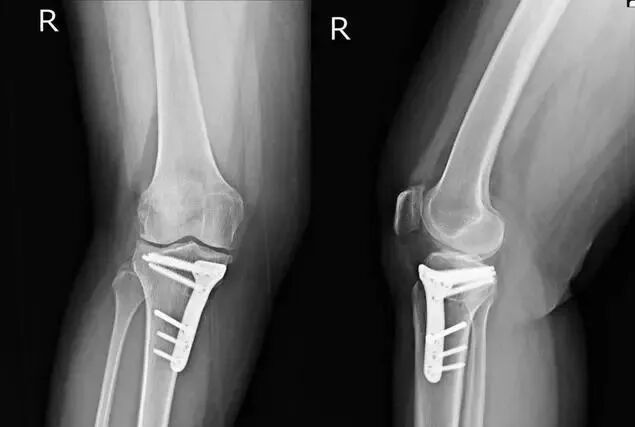

遇到了骨折患者术后钢板断裂,螺钉松动。面对这种情况,大多数患者会提出以下问题:“为什么这么结实的钢板会断”,“断了以后该怎么办?”

骨折或缺损后,植骨通常需要一个稳定的装置来连接骨头,并使其愈合。愈合应该有一个保证,这样骨头就不会移动。所以在这个时候,我们通常使用钢板来固定骨头的断端或缺陷。钢板一旦固定,骨头的上端、下端、远端和近端就会稳定在一起。

如果骨头已经完全愈合,钢板断裂,或螺钉松动,此时不需要处理,因为骨头已经生长,骨头的功能已经恢复。所以钢板或螺钉,此时没有更好的效果,你可以选择拆除钢板或螺钉。当然,如果骨骼愈合不是很彻底,而且还没有完全愈合,松动的螺钉应该重新固定。事实上,骨折的固定范围仍然有限,如简单的骨折,那么骨折上下,可能至少有两三个螺钉固定,所以钢板的距离是确定的,如7厘米,8厘米。然而,如果骨缺损,钢板可能会跨过缺损段,在近端骨和远端骨,然后至少固定三个螺钉,此时其长度会更长。固定长度越长,受外力影响的机会就越大,越容易断裂和松动。